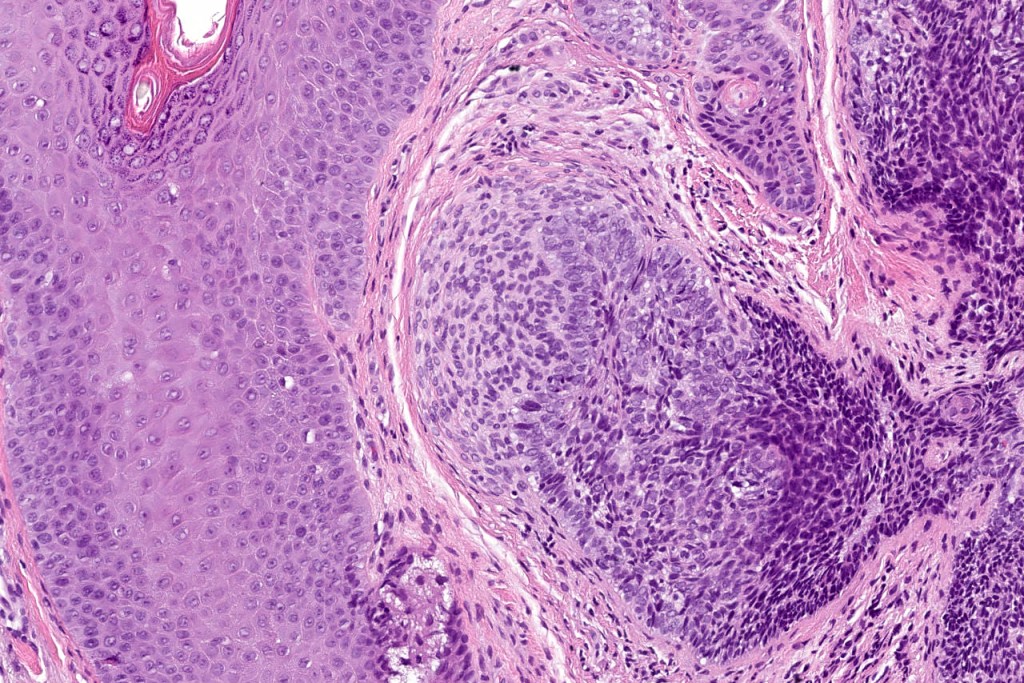

•The classical appearance consists of keratocysts & lobules of basaloid cells

•Basaloid lobules show peripheral palisading

•Retraction artifact and mucin deposition as seen in BCC are not present

•Perifollicular mesenchyme is always conspicuous and sometimes densely aggregated are seen indenting the baslaloid lobules (papillary mesenchymal bodies)

Trichoepithelioma should be distinguished from trichoblastoma since the latter is very rarely syndromic. Trichoepithelioma is largely a dermal tumor whereas trichoblastoma often extends from the dermis into subcutaneous fat or deeper in very large examples. Papillary mesenchymal bodies are much better formed and generally more obvious in trichoepithelioma. Trichoepithelioma must also be distinguished from basal cell carcinoma. Retraction artifact & stromal mucin are features of basal cell carcinoma and not trichoepithelioma. Papillary mesenchymal bodies are not seen in basal cell carcinoma.